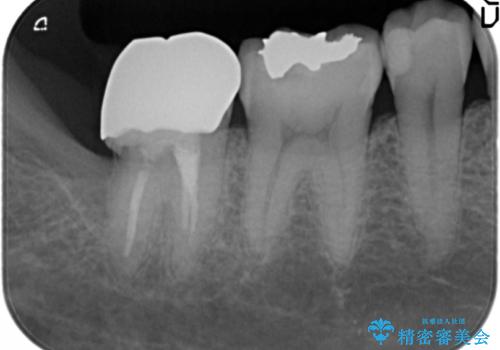

精査したところ、右下の一番奥の歯(右下7)に歯肉縁下に及ぶ深いう蝕を認めました。

神経がない歯であり痛みが出ないことから、自覚症状がほとんどなくう蝕が大きく進行してしまったと考えられます。

銀歯を除去し、歯周外科処置(右下7遠心の骨整形及びディスタルウェッジ)を行った後にメタルボンドクラウンによる補綴を行いました。

隣の歯(右下6)はセラミックインレーで修復しました。